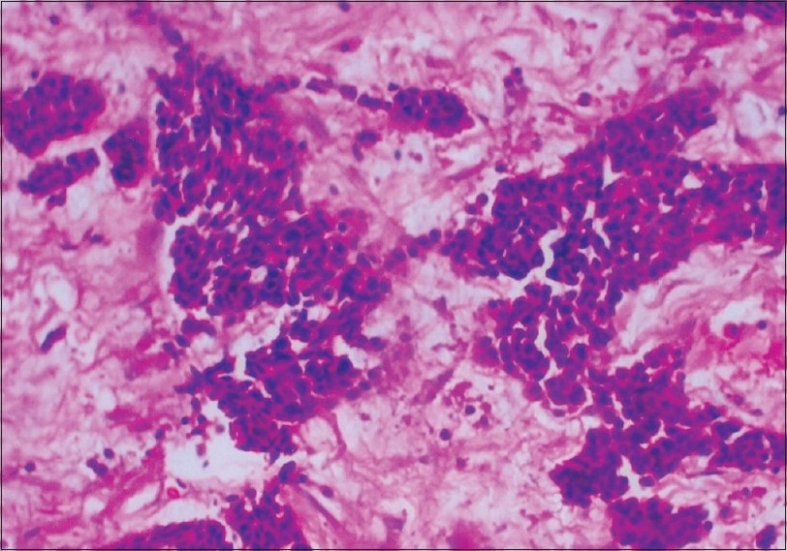

Microscopically, the majority of cells were small with scanty cytoplasm and hyperchromatic nuclei, admixed with occasional nucleoli arranged in nests with a focal cribriform pattern and trabeculae separated by desmoplastic stroma. Mitosis was scanty and necrosis was absent [Figures [Figures11 and and2].2]. No lymphovascular or perineural invasion was seen. Two areas of in-situ component were also noted showing cells of similar morphology. Immunohistochemistry was negative for neuron-specific enolase, chromogranin and synaptophysin, while it was positive for cytokeratin.

| Figure 2 High-power view of primary mammary cell carcinoma — H and E stain, (magnification ×200): High-power magnification photomicrograph showing small cells with prominent hyperchromatic nuclei with evenly distributed chromatin, scanty cytoplasm and occasional mitosis